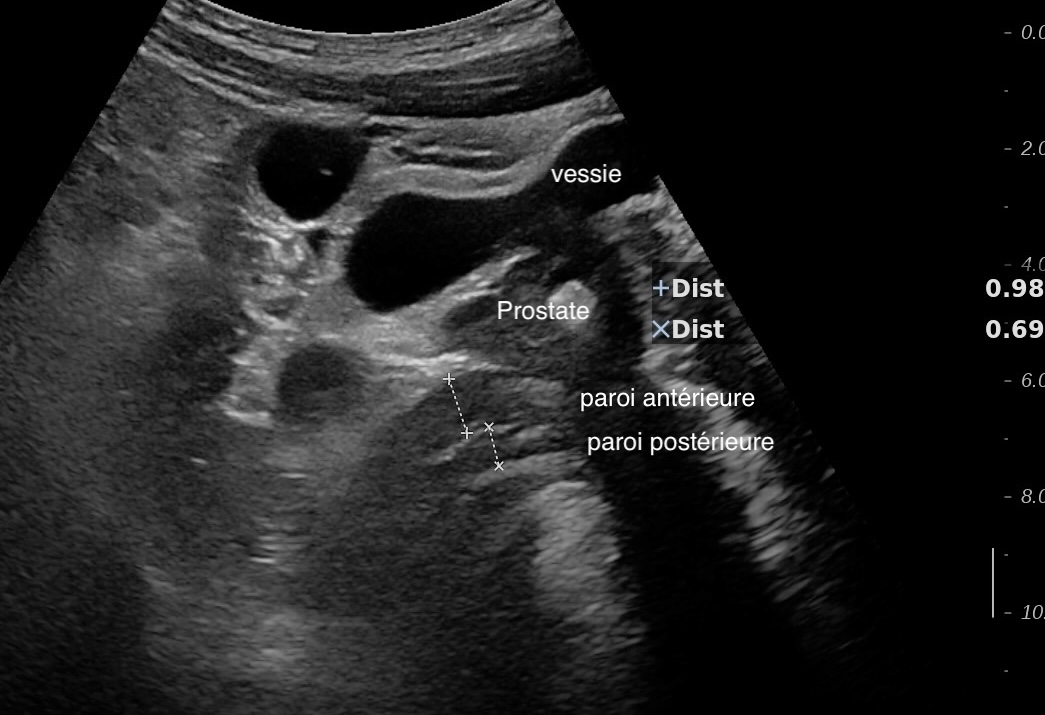

Là encore la paroi est très hypoéchogène, la structure en couches est par endroit totalement absente, ulcérations en surface, infiltration de la graisse, doppler intense, petites adénopathies périphériques.

Le rectum est bien vu avec la sonde basse fréquence la paroi atteint 10 mm à ce niveau.

Le score de Milan MUC est de (10 x1,4+2) = 16